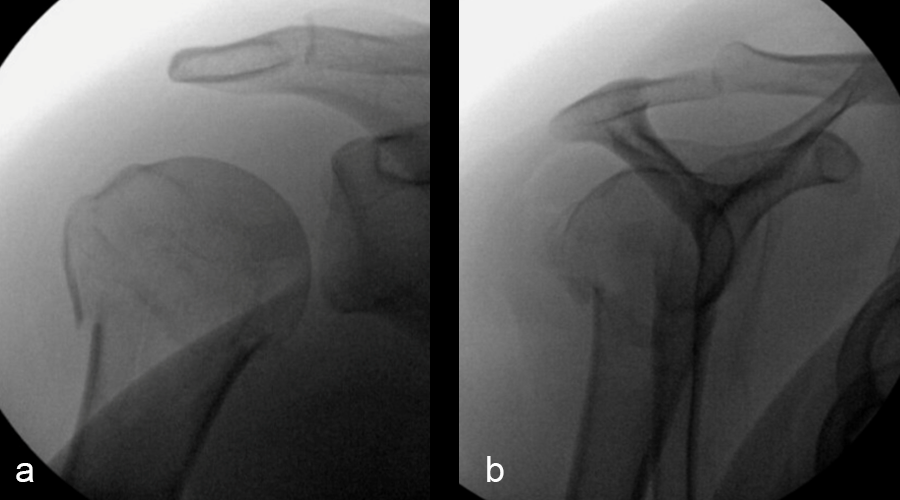

A 24-year-old woman presented to the emergency room following a motor vehicle accident. X-rays on the day of admission (Fig 1a-c) showed a fracture to the proximal humerus. There was some varus displacement of the humerus with involvement of the surgical neck and greater tuberosity.

The patient was treated with open reduction and internal fixation (ORIF). First, the fracture was reduced (Fig 2a-b). There was an attempt at closed reduction with continued displacement. Then an open reduction through a deltopectoral approach was performed. After direct reduction, a 1.6 mm K wire was placed along the anterolateral humeral surface. The provisional plate placement and reduction are depicted in Fig 3.